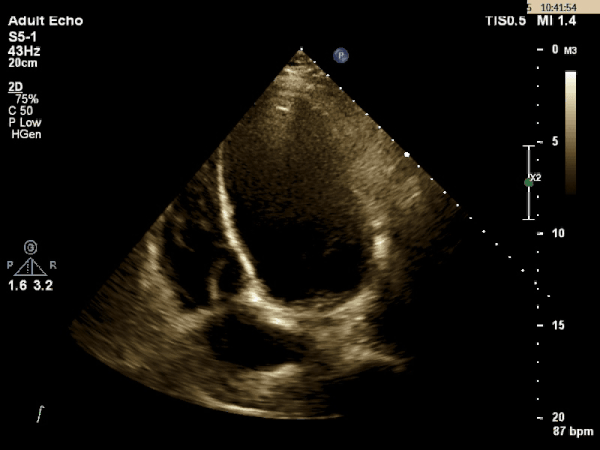

Echocardiogram